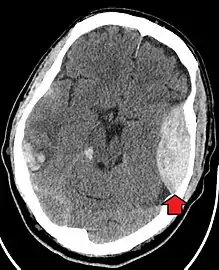

Epidural hematoma as seen on a CT scan with overlying skull fracture. Note the biconvex shaped collection of blood. There is also bruising with bleeding on the opposite side of the brain.

Epidural hematomas usually appear convex in shape because their expansion stops at the skull's sutures, where the dura mater is tightly attached to the skull. Thus, they expand inward toward the brain rather than along the inside of the skull, as occurs in subdural hematomas. Most people also have a skull fracture.[3]